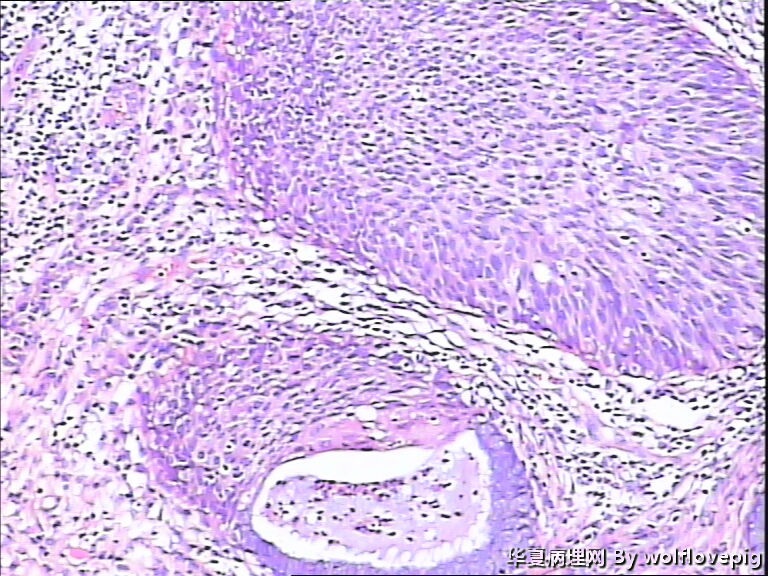

求助,宫颈!

37y

CIN3累腺

CINIII累及腺体